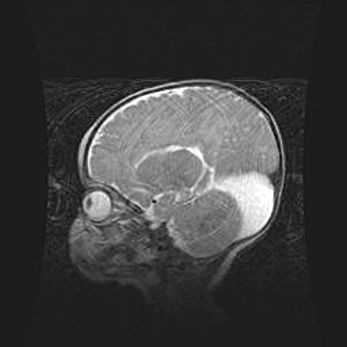

Аномалия Денди-Уокера. Признаки гипоплазии мозолистого тела.

Возраст: 5 месяцев 3 дня

Вес: 5550 г

Пол: мужской

Окружность головы: 39 см

Срок гестации: 40 недель

Аномалия Денди-Уокера – это порок развития головного мозга, для которого характерна триада симптомов: гипотрофия или аплазия червя мозжечка и/или полушарий мозжечка, расширение четвёртого желудочка с формированием ликворной кисты задней черепной ямки, гипертензионная гидроцефалия различной степени.

Гипоплазия мозолистого тела относится к дефектам внутриутробного этапа развития мозговой ткани, возникающим в процессе закладки структур головного мозга, что происходит на начальных этапах развития эмбриона.